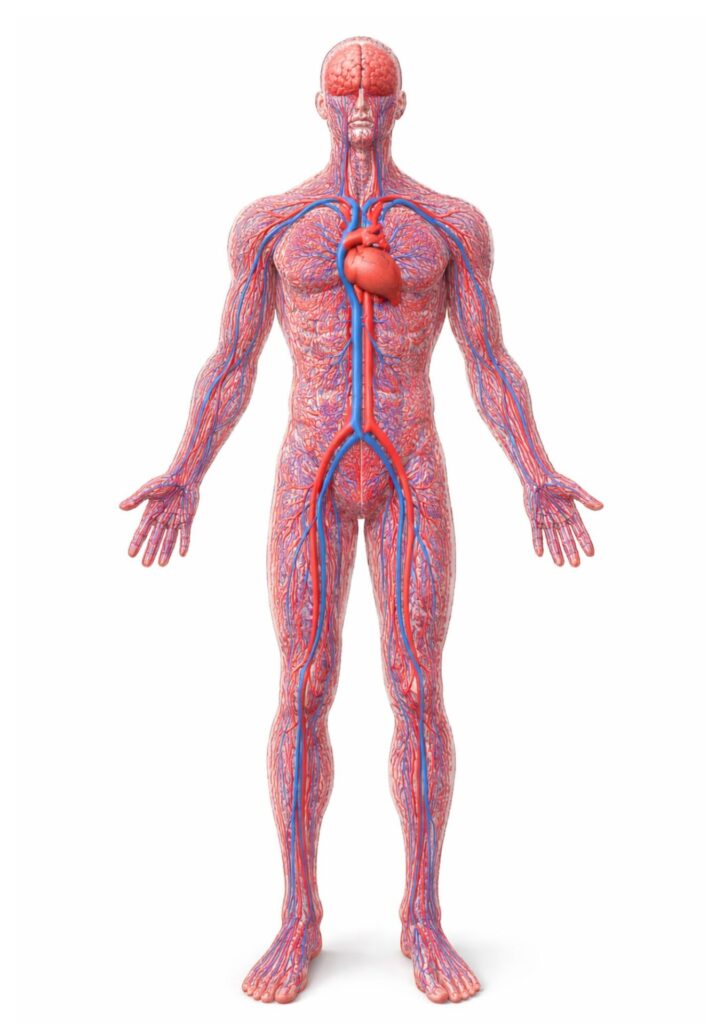

血液は、毛細血管を通して全身の細胞に酸素や栄養を届け、老廃物を回収しています。

毛細血管は“全身の物流センター”

毛細血管は、細胞へ 酸素・栄養を届け、代謝で出た 老廃物を回収する現場。

体の調子は「細胞が元気かどうか」に左右されやすく、毛細血管はその土台になります。

毛細血管は“細い・多い・長い”

指先の毛細血管は非常に細く、最も細い部分は約 5μm 程度とも言われます。

また毛細血管は全身の血管の大部分を占め、長さは 地球2周半(約10万km) と表現されることもあります。